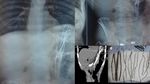

Seorang bocah empat tahun dilarikan ke rumah sakit karena mengalami nyeri perut selama 5-6 jam. Setelah dilakukan pemeriksaan, rontgen menunjukkan benda asing lingkaran berupa koin yang tidak sengaja tertelan. (Foto: F1000 Research)

Seorang tukang kayu tidak sengaja menelan sekrup dan mengeluhkan gejala nyeri ringan perut kanan bawah. Untungnya, dokter tidak menemukan kelainan berarti sehingga sekrup itu dikeluarkan tanpa masalah. (Foto: F1000 Research)

Seorang pria 25 tahun datang menjalani pemeriksaan USG dengan keluhan nyeri perut selama 2-3 bulan. Setelah dilakukan CT scan, dokter menemukan benda logam dalam perutnya. Saat dilakukan laparoskopi, ditemukan banyak isi ulang pulpen dan kawat di dalam lambung pasien. (Foto: F1000 Research)